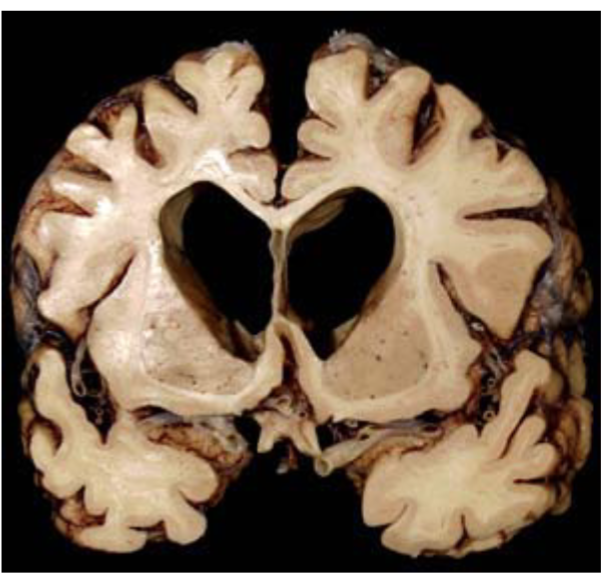

What pathology is shown in the provided image?

Cortical atrophy (consistent with Alzheimer disease)